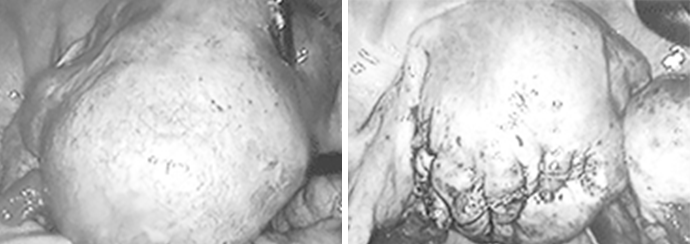

자궁내막증 수술

자궁내막증은 기능이 있는 자궁내막조직이 자궁이 외의 부위에 존재하는 만성 재발성 양성 질환으로 가임 여성의 10%, 난임 여성의 30%정도에서 발견됩니다. 진행된 중증의 자궁내막증은 난관폐쇄, 자궁부속기 유착 등을 일으켜 난관의 운동, 난관 내로의 난자 유입, 배란에 영향을 주어 난임의 원인이 될 수도 있고, 난포의 생성, 수정, 면역 및 착상에도 영향을 줄 수 있습니다. 또한 만성적인 하복부 통증과 심한 생리통 및 성교 시 통증은 삶의 질(quality)에도 심각한 영향을 줄 수 있습니다. 자궁내막증 진단의 최상의 방법은 복강경이며, 복강경을 통하여 자궁내막증 병변을 절제하거나 소작하고, 골반 장기의 유착을 제거하여 정상적인 골반구조를 회복할 수 있습니다.

또한 자궁내막증에 의한 난소 낭종을 제거함으로써 임신율을 높일 수 있고 통증을 경감시킬 수 있습니다. 수술 전후로 호르몬 치료를 3-6개월 정도 시행할 수도 있습니다.